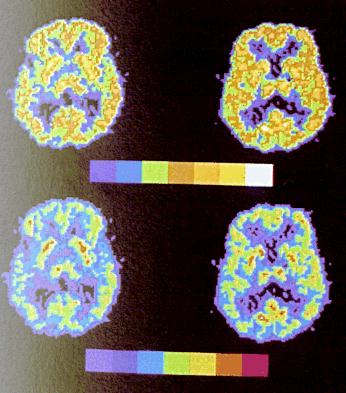

One method to improve information visibility is the use of pseudocolor, i.e., the mapping of one or more attributes of the information to color. So each value, or range of values corresponds to some color. A common method is to use the rainbow scale, i.e., the assignment is based on the position of the color in the visible spectrum (violet - blue for low values up to red for high values). This scale is based on hue contrast. Some studies have indicated that a scale based on brightness contrast is more effective. The brightness is based on the perceived brightness rather than the physical brightness.

| Here is an example of two sets of data images, with the upper pair based on brightness contrast and the lower pair based on hue contrast. | ![]() |

Studies also show that, for colored objects, bright objects on a dark background look bigger than the same objects depicted with dark colors on a bright background. In the above image notice that the green spots in the lower left hand image look larger than the orange spots in the upper left image. There are two implications: care must be taken when making quantitative estimates from the visual data, and small objects can be made more visible by make them brightly colored against a dark background.